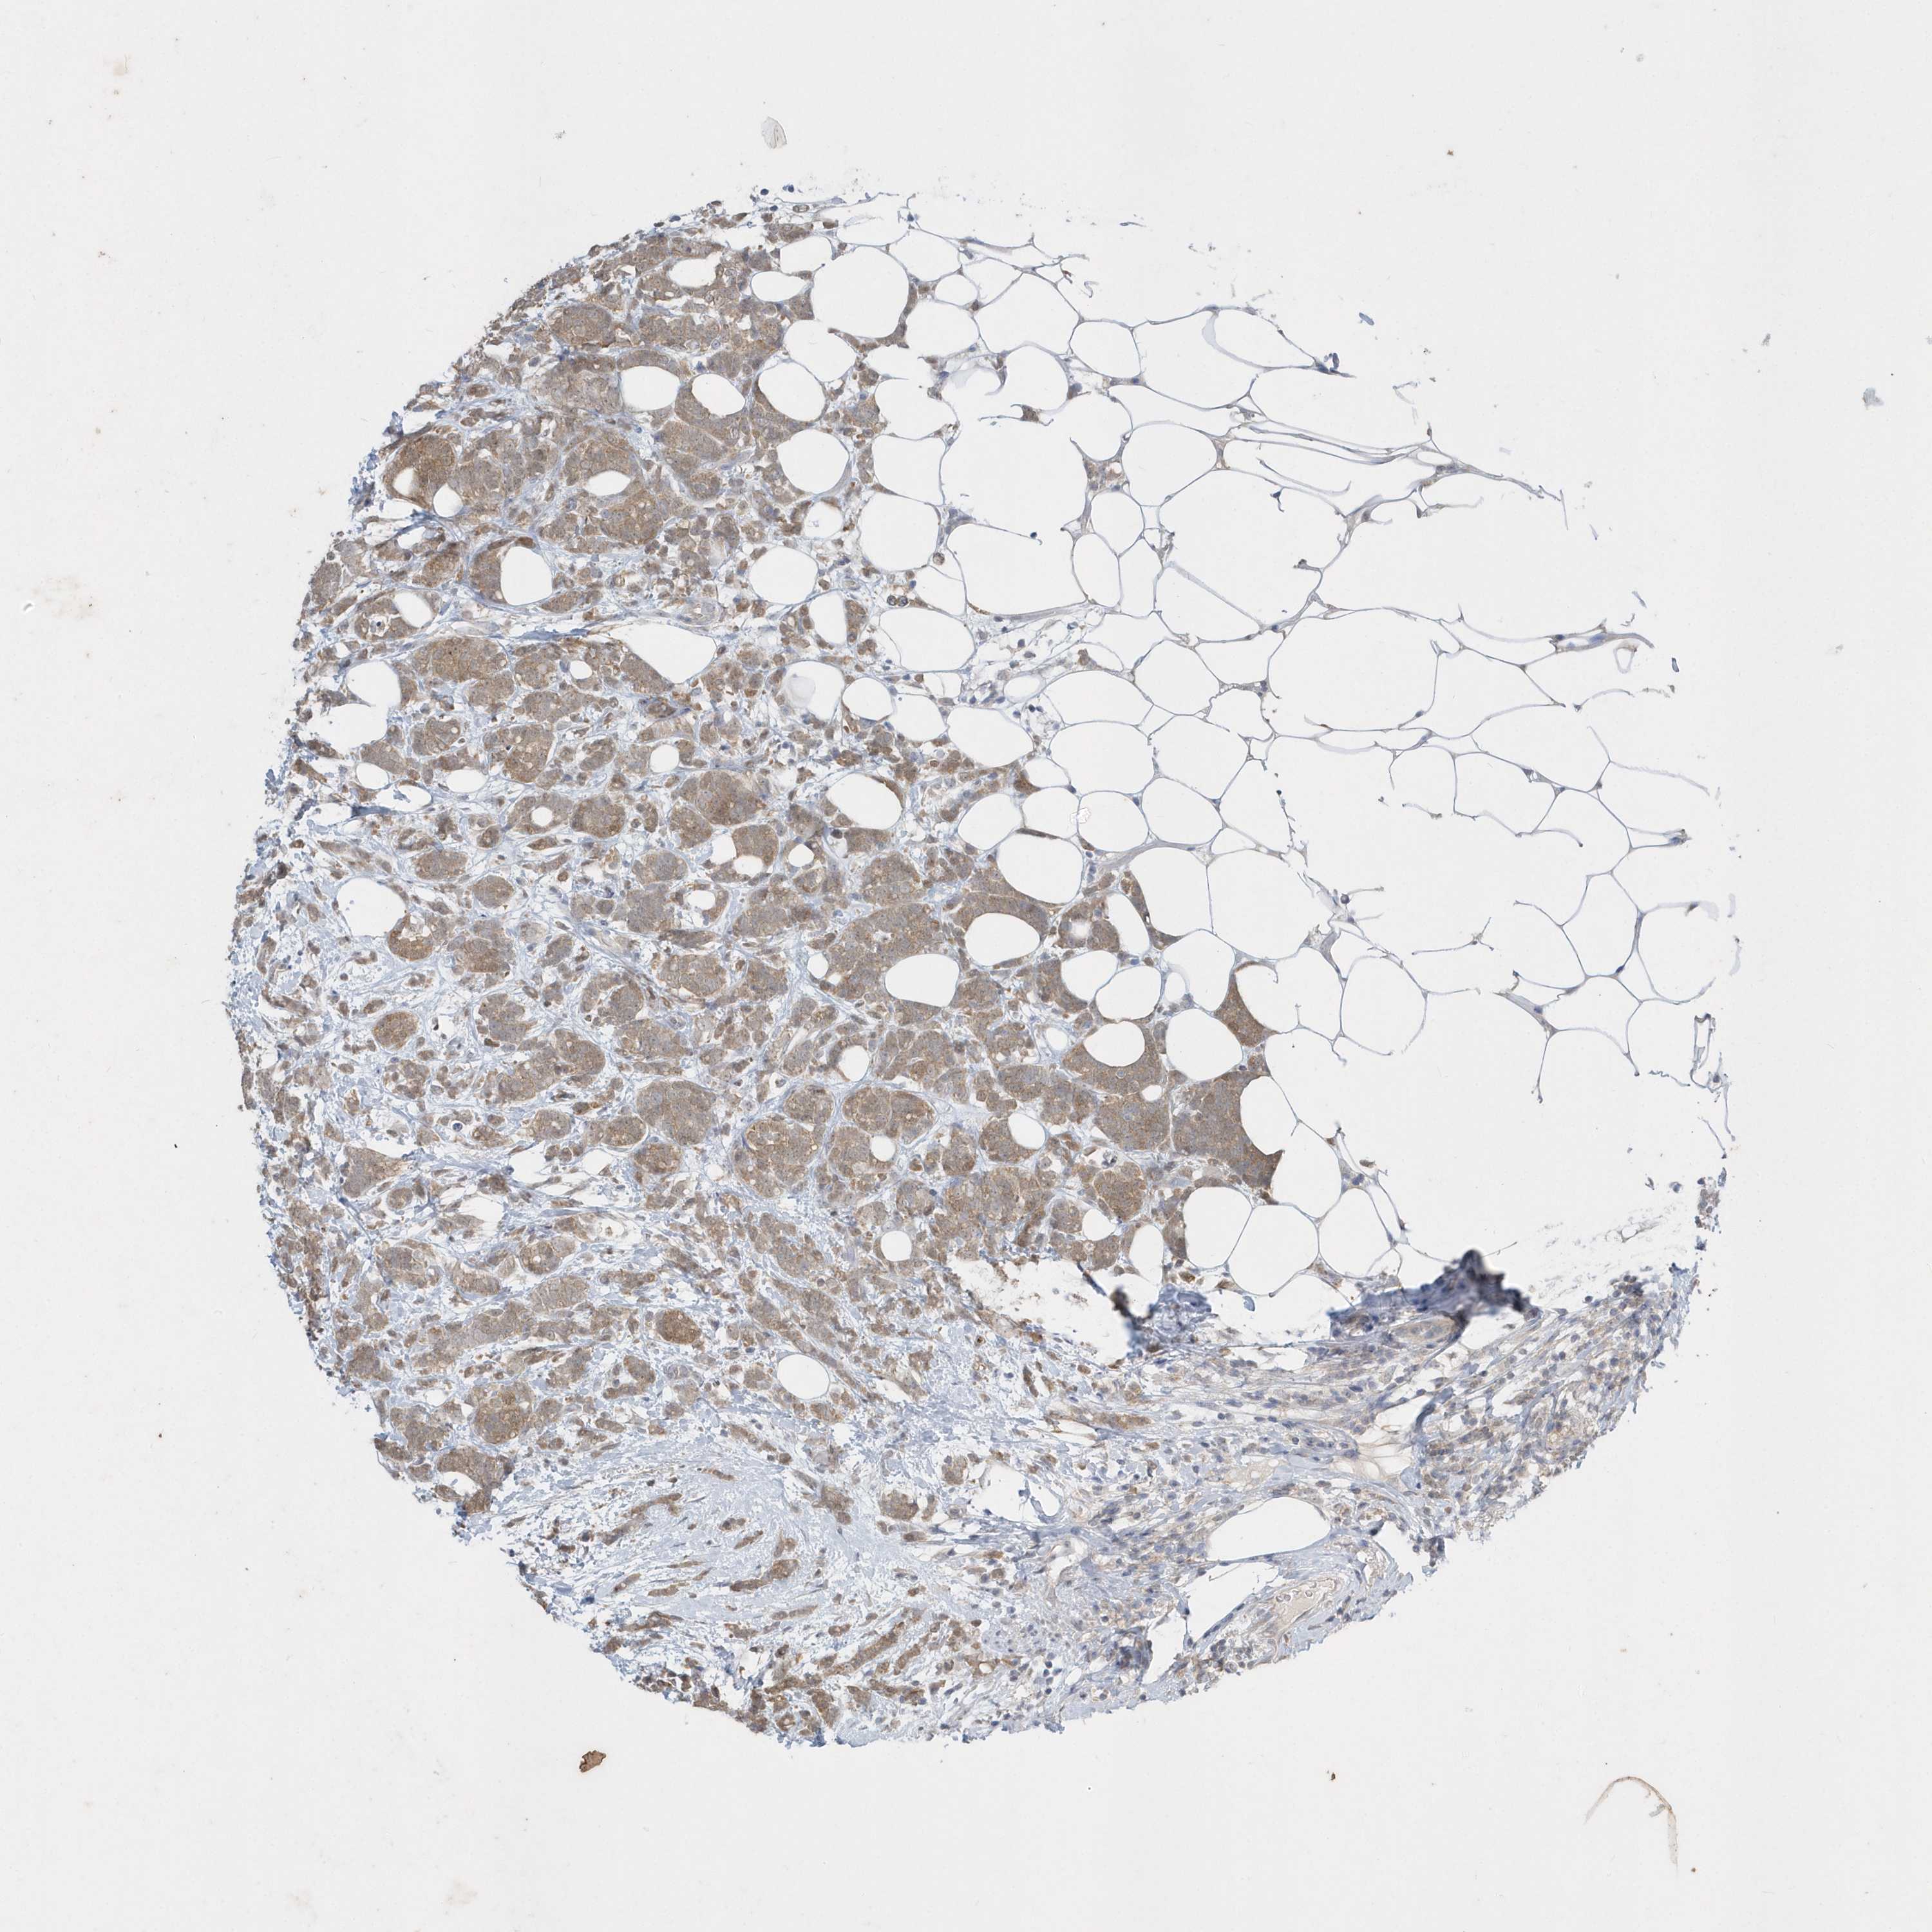

BRCA TCGA BRCA VALIDATION PROTEIN EXPRESSION